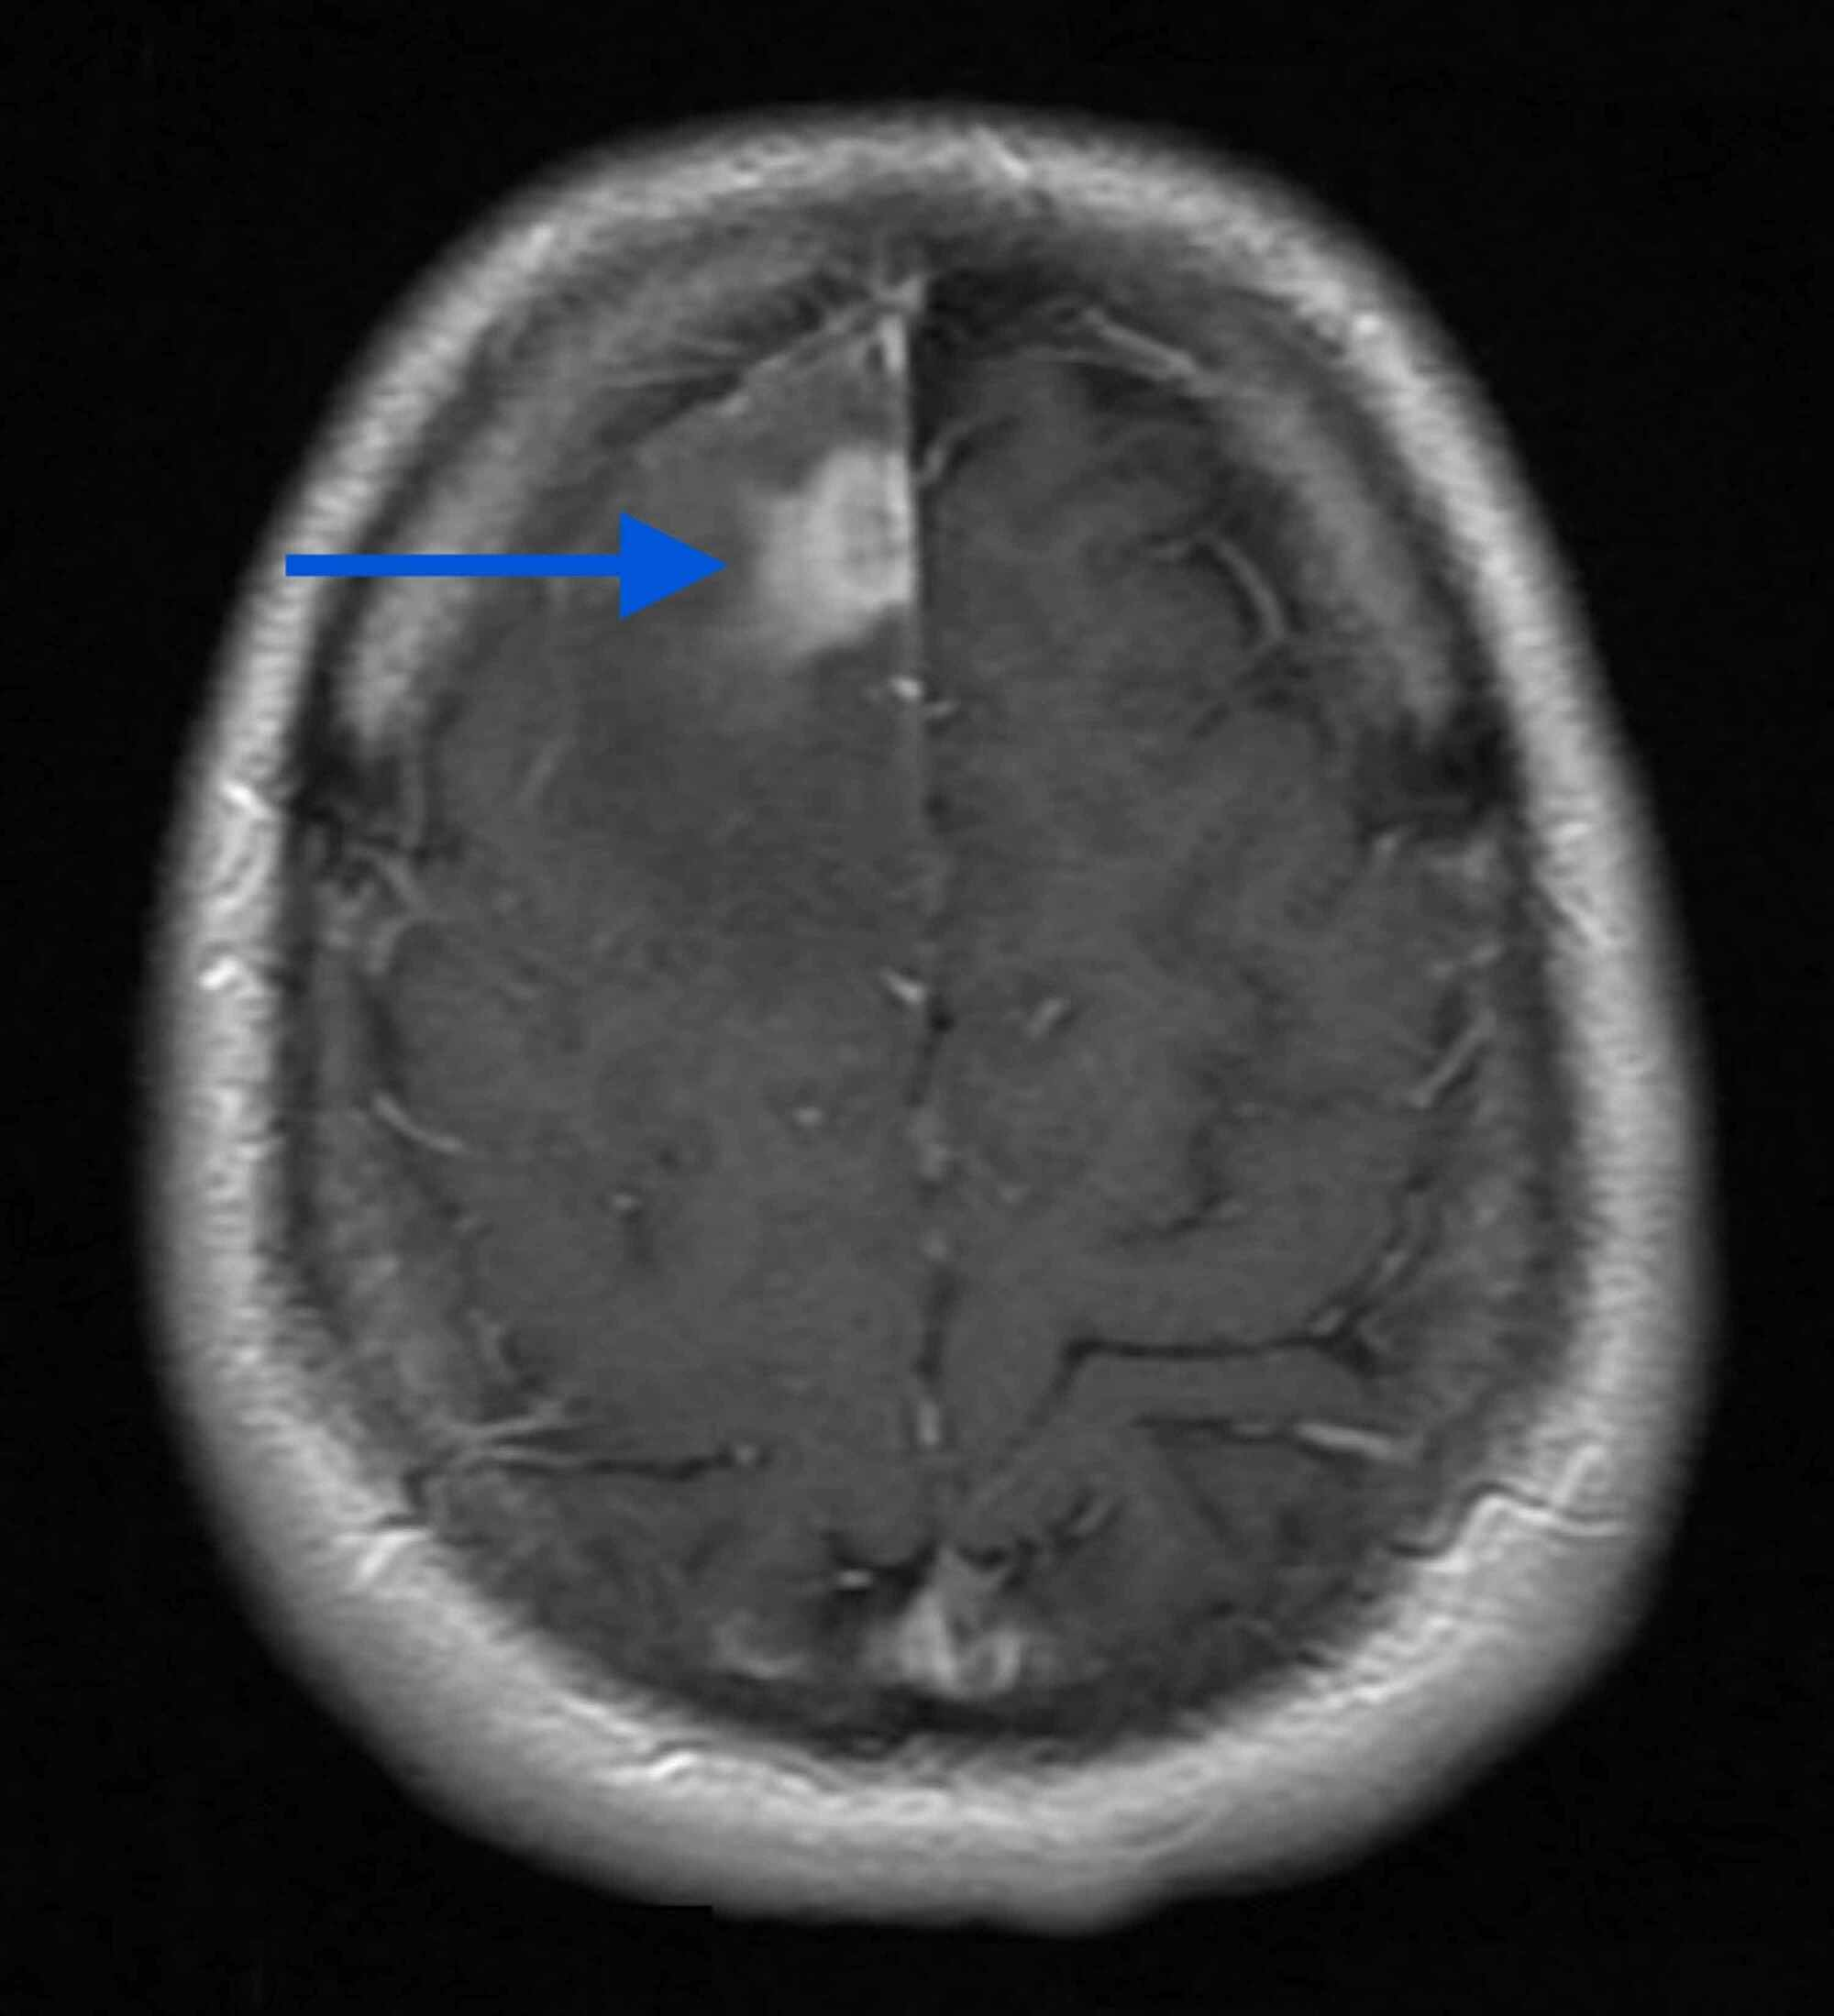

Swiss cheese brain presenting as corticobasal syndrome Neurological

Swisscheese appearance of the brain in a young boy BMJ Case Reports Swiss Cheese Brain Mri Despite the diverse etiologies, vrs have not been previously documented as a cause of cbs. The classic mr appearance of radiation necrosis is depicted as an enhancing. Dynamic susceptibility contrast (dsc) mri is the most widely used perfusion technique for brain tumors. Colloquial descriptions of rn on mri include “soap bubble,” “cut green pepper,” or “swiss cheese,” though the positive. Swiss Cheese Brain Mri.

Swiss cheese brain presenting as corticobasal syndrome Neurological Swiss Cheese Brain Mri Colloquial descriptions of rn on mri include “soap bubble,” “cut green pepper,” or “swiss cheese,” though the positive predictive. Despite the diverse etiologies, vrs have not been previously documented as a cause of cbs. Dynamic susceptibility contrast (dsc) mri is the most widely used perfusion technique for brain tumors. In practice, the low predictive value of conventional mr features prompted. Swiss Cheese Brain Mri.

Swisscheese appearance of the brain in a young boy BMJ Case Reports Swiss Cheese Brain Mri The classic mr appearance of radiation necrosis is depicted as an enhancing. Colloquial descriptions of rn on mri include “soap bubble,” “cut green pepper,” or “swiss cheese,” though the positive predictive. Dynamic susceptibility contrast (dsc) mri is the most widely used perfusion technique for brain tumors. Despite the diverse etiologies, vrs have not been previously documented as a cause of. Swiss Cheese Brain Mri.

(PDF) The Swiss cheese brain Swiss Cheese Brain Mri In practice, the low predictive value of conventional mr features prompted the need for more advanced tools, such as mr. The classic mr appearance of radiation necrosis is depicted as an enhancing. Dynamic susceptibility contrast (dsc) mri is the most widely used perfusion technique for brain tumors. The “swiss cheese brain” appearance. Despite the diverse etiologies, vrs have not been. Swiss Cheese Brain Mri.

(PDF) The Swiss cheese brain Swiss Cheese Brain Mri Despite the diverse etiologies, vrs have not been previously documented as a cause of cbs. The “swiss cheese brain” appearance. The classic mr appearance of radiation necrosis is depicted as an enhancing. Dynamic susceptibility contrast (dsc) mri is the most widely used perfusion technique for brain tumors. Colloquial descriptions of rn on mri include “soap bubble,” “cut green pepper,” or. Swiss Cheese Brain Mri.

(PDF) The Swiss cheese brain Swiss Cheese Brain Mri The classic mr appearance of radiation necrosis is depicted as an enhancing. Dynamic susceptibility contrast (dsc) mri is the most widely used perfusion technique for brain tumors. The “swiss cheese brain” appearance. In practice, the low predictive value of conventional mr features prompted the need for more advanced tools, such as mr. Despite the diverse etiologies, vrs have not been. Swiss Cheese Brain Mri.